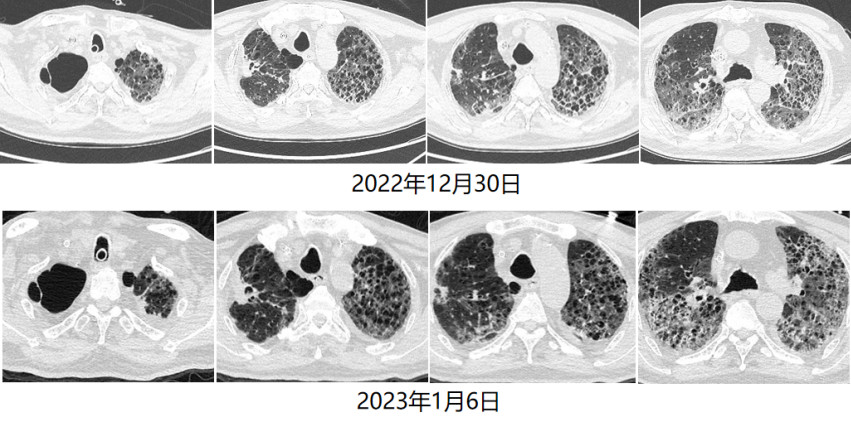

循环方面:患者心功能可,容量状态略微偏低,故未予过多限液。呼吸支持及氧合变化:12月28日建立VV-ECMO后患者的通气和氧合均得到明显改善,随着支持条件的逐渐下降,PaO2均可。患者于2023年1月6日行V-V ECMO心肺试验(cardiac-pulmonary test,CPT),在2 h时,患者血气分析、氧合指数能够维持,且无呼吸窘迫情况出现。1月6日复查胸部CT:双肺渗出吸收不理想,双下肺病变较前无明显变化。